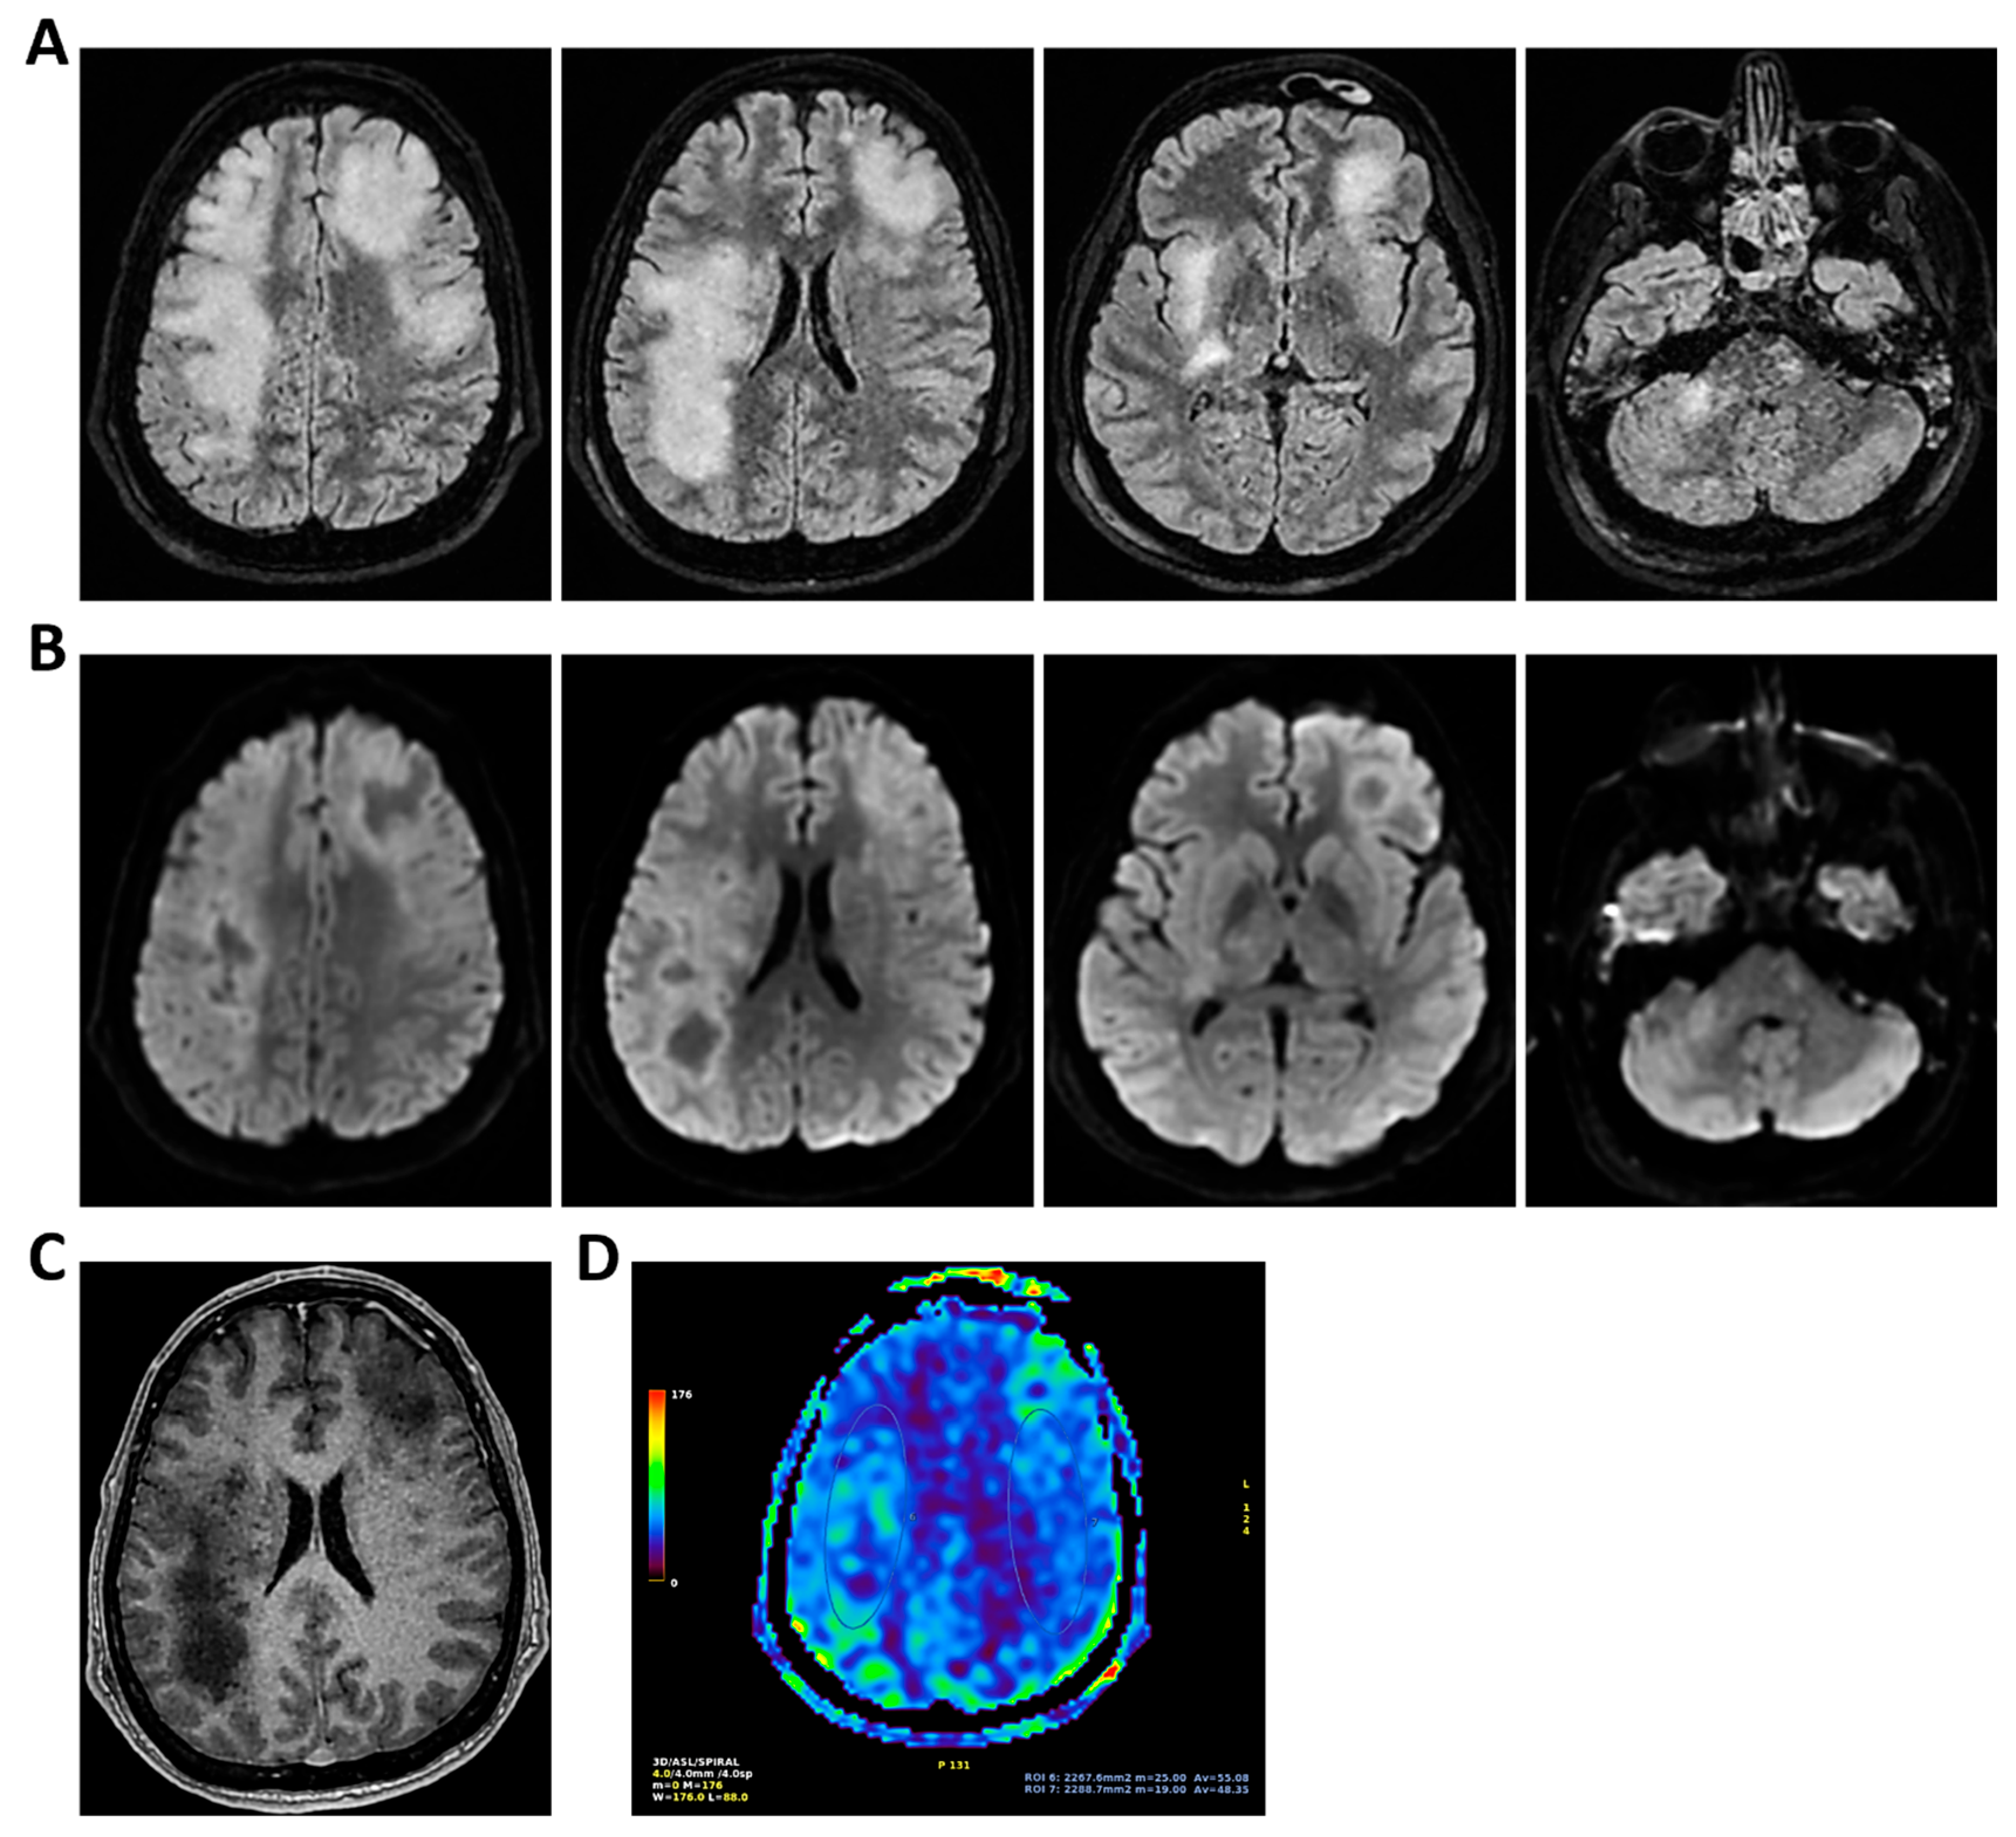

Figure 1.

MRI of patient 1 group 1. A 74-year-old woman with a history of atrial fibrillation, ischemic heart disease, anxiety-depressive syndrome, and hypertension was found at home in a stuporous state. She had experienced asthenia and fever in the preceding days and had initiated ciprofloxacin treatment. On arrival, laboratory exams showed leukocytosis (11,930/mm3, 90.4% neutrophils), elevated INR (1.92), and markedly increased inflammatory markers. Arterial blood gas revealed hypoxemia (pO2 55 mmHg), requiring mechanical ventilation with 35% FiO2. Brain CT was unremarkable, showing no acute lesions or signs of raised intracranial pressure. Chest CT revealed bilateral posterior-basal consolidations with air bronchograms (more severe on the left), a smaller consolidation in the left upper lobe, and bilateral pleural effusions, consistent with bronchopneumonia. A lumbar puncture was initially contraindicated due to coagulopathy. Due to worsening neurological status (GCS 6), the patient was transferred to the ICU, intubated, and underwent lumbar puncture. On day 2, TCCD showed PI values of 0.62 (right) and 0.71 (left), with no signs suggestive of intracranial hypertension. (A) 3D axial FLAIR sequence shows multiple bilateral hyperintense areas, without mass effect. (B) Some of these present diffusion restriction in axial DWI sequence with the largest located in the left middle and superior frontal gyrus. There is also a subtle pachymeningeal enhancement in the bilateral fronto-temporal region. Supratentorial and infratentorial ventricular system is normal in size and configuration, with no midline shift or hydrocephalus.

Figure 6.

MRI of patient 1 group 2. A 63-year-old man with a history of hypertension, dyslipidemia, and prior pulmonary lobectomy was admitted to the ER in a drowsy but verbally responsive state. His wife reported a recent episode of vomiting followed by loss of consciousness and tonic–clonic seizures. He was uncooperative and tremulous but afebrile, although a febrile episode had occurred in the preceding days. A lumbar puncture led to a diagnosis of Neisseria meningitidis type B meningitis. Ceftriaxone 2 g IV every 12 h was initiated. Brain CT, chest CT, and angio-CT of the epiaortic vessels showed no acute abnormalities. Due to clinical deterioration and a further seizure with hypotension, the patient was sedated, intubated, and experienced an episode of ventricular tachycardia during CT imaging, requiring IV Amiodarone. The patient was transferred to the ICU. On day 2, TCCD showed no significant flow abnormalities, with only mild asymmetry in PI (1.11 right, 1.4 left), without evidence of intracranial hypertension. (A) MRI exam with perfusion study reveal areas of altered signal intensity, hyperintense on 3D axial FLAIR sequence, (B) with diffusion restriction in axial DWI sequence, indicative of subacute inflammatory processes. These areas were scattered, the most significant is located along the subpial cortical surfaces of the left precentral and supramarginal gyri. Additionally, MRI exam demonstrates leveled material of likely inflammatory nature in both occipital horns of the lateral ventricles (A,B). (C) MRI perfusion with ASL sequence shows normal and symmetrical CBF values. Blue circles indicate the region of interest (ROI) used for quantitative CBF analysis.

Figure 9.

MRI of patient 4 group 2. A 35-year-old HIV-positive man, diagnosed in 2018 with pneumocystosis (PCP) and non-compliant with Highly Active AntiRetroviral Therapy (Biktarvy), presented with bilateral otalgia, progressive hearing loss, left-sided hemiparesis, and impaired coordination. He was hospitalized and reinitiated Biktarvy and PCP prophylaxis with Bactrim. He received broad-spectrum antibiotics for bilateral otomastoiditis and ganciclovir for CMV viremia. Brain MRI revealed findings consistent with progressive multifocal leukoencephalopathy (PML). After discharge, worsening left hemiparesis and new-onset dysarthria led to readmission. A follow-up CT showed progression of subcortical white matter lesions. Lumbar puncture, urine, and plasma were all positive for JC virus. The patient was transferred to the ICU for further management. On day 2, TCCD showed PI of 1.50 on the right and 1.07 on the left, indicating mild asymmetry but no definitive signs of intracranial hypertension. (A) MRI exam shows large areas of altered signal intensity, without significant mass effect, hyperintense in 3D axial FLAIR sequence, (B) with peripherical diffusion restriction in axial DWI sequence, (C) without contrast enhancement in 3D axial T1 FSPGR, involving both cortical and deep regions of the frontal, temporal and parietal regions bilaterally, as well as right insular and thalamic regions. Additionally, the brainstem with left-sided predominance and the right middle cerebellar peduncle are involved. These alterations are consistent with PML. (D) MRI perfusion study documents minimal increase in CBF in the more cranial regions on the right. Blue circles indicate the ROI used for quantitative CBF analysis.

Figure 10.

MRI of patient 5 group 2. A 67-year-old woman with schizophrenia presented to the ER with lethargy and vomiting, following 10 days of fever and dry cough treated ineffectively with Medrol and Cefditoren. Brain CT showed a left temporoparietal hypodensity (sequela) and supratentorial ventricular dilation without midline shift. The lumbar puncture was positive for Listeria monocytogenes (FilmArray). Due to neurological deterioration (GCS 7), she was transferred to the ICU. On day 2, TCCD showed PI values of 1.65 (right) and 1.89 (left), indicating increased cerebral vascular resistance without clear signs of intracranial hypertension. (A) 3D axial FLAIR shows marked and diffuse atrophy of the brain tissue, more pronounced in the left hemisphere where some areas of enlargement of the cerebrospinal fluid spaces are observed, more prominent in the parietal region, and diffuse dilation of the supraventricular system, particularly in the occipital horns. (B) Perfusion study reveals minimal asymmetry in cerebral perfusion values sampled at the level of the semioval centers. Blue circles indicate the ROI used for quantitative CBF analysis.

3.1. Group 1: TCCD and Standard MRI (FLAIR and DWI)

Regarding etiology, two cases, case 1 and 5 (40%), were due to pneumococcal meningitis, while the remaining were neurotoxoplasmosis (n = 1, 20%) (case 2), Varicella-Zoster virus meningoencephalitis (n = 1, 20%) (case 3), and meningoencephalitis of undetermined origin (n = 1, 20%) (case 4). Three out of five patients demonstrated normal or mildly elevated pulsatility indices (PI ≤ 1.18) and no waveform signs of intracranial hypertension. In these cases, MRI findings were either normal or showed non-specific alterations, such as mild pachymeningeal enhancement or limited subcortical lesions, without mass effect or restricted diffusion. All three patients in this subgroup experienced full neurological recovery at 28 days (GOS 5) (Table 2 and Figure 1, Figure 2 and Figure 3).

In contrast, two patients in the same group presented with elevated PIs. One patient with HIV and neurotoxoplasmosis exhibited bilateral flow abnormalities (PI 1.96 on the right; 1.25 on the left), with multiple supratentorial ring-enhancing lesions on MRI, suggestive of cerebral toxoplasmosis. The patient showed no significant clinical improvement at 28 days (Table 2 and Figure 4).

Another patient with Varicella-Zoster meningoencephalitis had a critically elevated left-sided PI (3.6) and MRI findings limited to hippocampal hyperintensity (Table 2 and Figure 5).

Despite subtle structural abnormalities, the patient died within 28 days of admission. In both cases, high PI values accompanied poor neurological outcomes, highlighting the prognostic role of TCCD in identifying impaired cerebrovascular reserve and autoregulation failure.